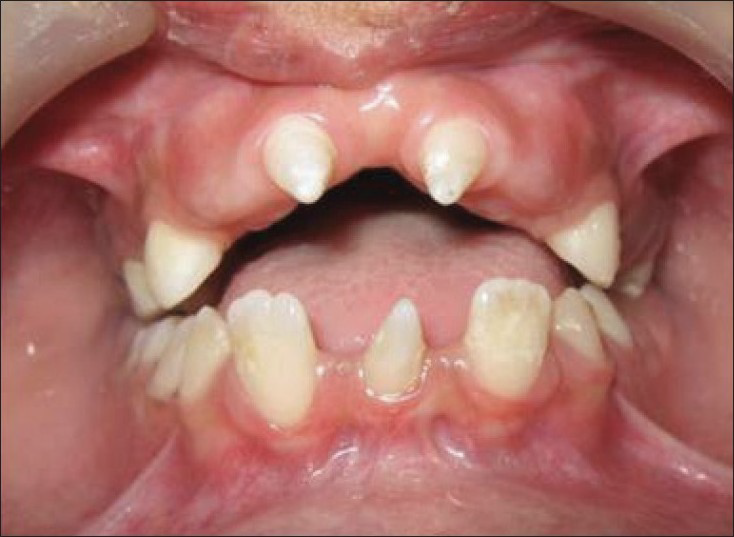

數量異常

缺牙

hypodontia

缺牙症,缺不超過6顆牙

oligodontia

少牙症

anodontia

無牙

mesiodens

Supernumerary teeth (多生牙)

conical/ peg-shaped teeth (Ectodermal Dysplasia)